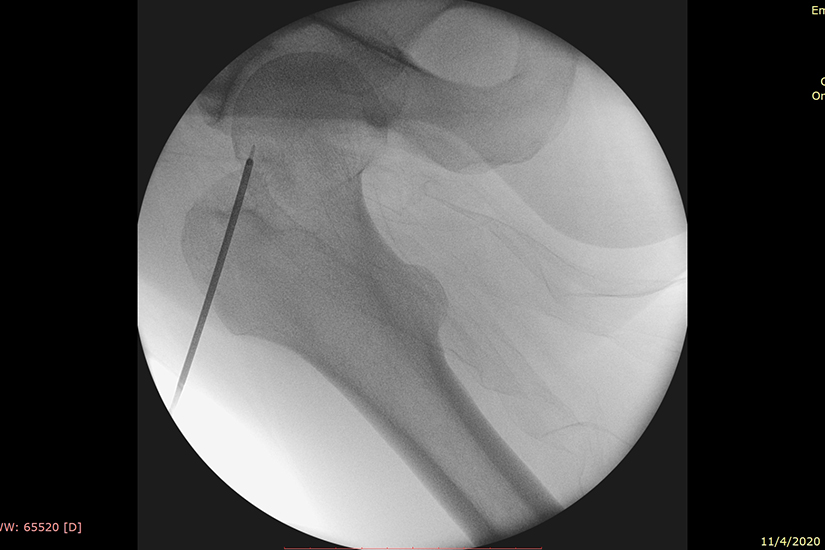

Procedura chirurgicala a constat in introducerea percutanata, sub control radiologic, a unei sonde in centrul formatiunii tumorale, care apoi a fost distrusa prin ablatie tumorala prin radiofrecventa cu ajutorul unui sistem ultramodern denumit OsteoCool oferit de Medtronic Somafor Danek. Interventia a fost realizata de doi dintre chirurgii ortopezi cu vasta experienta in cele mai noi si moderne tehnici chirurgicale din Spitalul Puls din Targu Mures: si dr. Bogdan Voicu. dr. Adrian Blesneac

In cazul interventiei de ablatie percutanata prin radiofrecventa, medicul chirurg patrunde prin piele fix in mijlocul tumorii. Procedura este frecvent folosita in Cardiologie, pentru tratamentul fibrilatiei atriale. In cazul de fata, medicii chirurgi au folosit un aparat asemanator, setat special pentru tesutul osos (OsteoCool).

“Practic, prin piele patrunzi fix in mijlocul tumorii, dupa care sonda se conecteaza la un aparat extern si efectiv arde tumora. Foarte important de mentionat este ca se foloseste o temperatura controlata, care nu depaseste mai mult de 70 de grade. In acelasi timp, tumora este si racita, deci este un proces continuu in care se mentine temperatuta constanta. Nu este ca si cum am lega un electrod si il punem la curent electric si-l ardem si nu conteaza temperatura, pentru ca daca depasim o anumita temperatura, conform studiilor, poti distruge si tesutul inconjurator – de aceea ai nevoie de un mediu controlat. Sigur, acest lucru este realizat automat de aparat”, explica dr. Adrian Blesneac.

“A durat foarte mult pregatirea pacientului si pozitionarea acestuia, astfel incat sa putem ajunge la tumora deoarece vorbim de o zona mai delicata-colul femural. A fost nevoie de o masa speciala de operatie, avand in vedere ca pentru sold este nevoie de o masa ortopedica speciala in care piciorul se pune intr-o anumita pozitie. De asemenea, tintirea centrului tumorii este o etapa dificil de realizat”, explica dr. Adrian Blesneac.